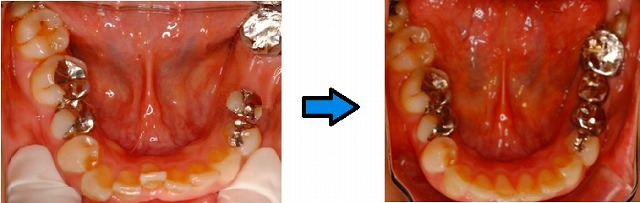

見た感じはただ入れただけのように見えますが、実は前歯の重なりを無くすために小矯正をしています。インプラントのスペースを利用して少し狭めてやって、前歯の重なりをなくしています。

写真では、前歯が綺麗に並んでインプラントの所には少し小さめの歯が入っています。

患者様としては、重なっている部分の着色が気になっていましたが、矯正後は歯ブラシも当てやすくなり着色しなくなったとおっしゃっていました。